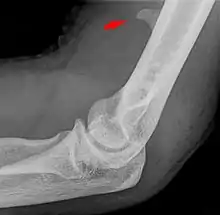

L’apophyse sus-épitrochléenne possède une forme approximativement pyramidale, elle est située à environ 6 cm (chez l’adulte) au-dessus de l’épitrochlée et à mi-distance des bords interne et antérieur de l’humérus[2]. La plupart du temps, une bandelette fibreuse fait suite à l’apophyse et forme avec elle un canal ostéofibreux où passe le nerf médian accompagné en général d’une artère[3].

L’apophyse sus-épitrochléenne peut parfois être symptomatique par la compression nerveuse entre l’apophyse osseuse et les masses musculaires environnantes. La fracture de l’apophyse sus-épitrochléenne peut également provoquer des lésions des éléments nerveux ou artériels passant à proximité[14].